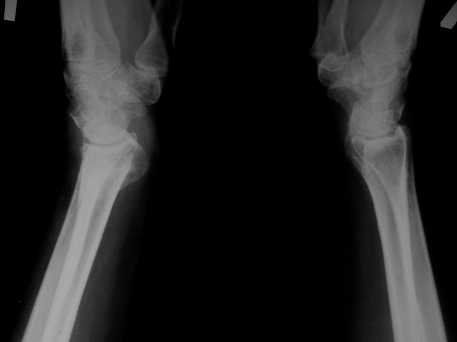

Обратилась женщина, 55 лет. Травма 3 месяца назад, лечилась по месту жительства (Рис.1). Косорукость, боли, ограничение движений. Досняли - рис.2-6. Хотелось-бы услышать мнения  об объеме операции.

Имя     : 4.JPG